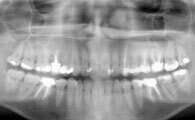

Une radio panoramique dentaire est un cliché radiographique de l'ensemble de la denture et des articulations temporo mandibulaires.